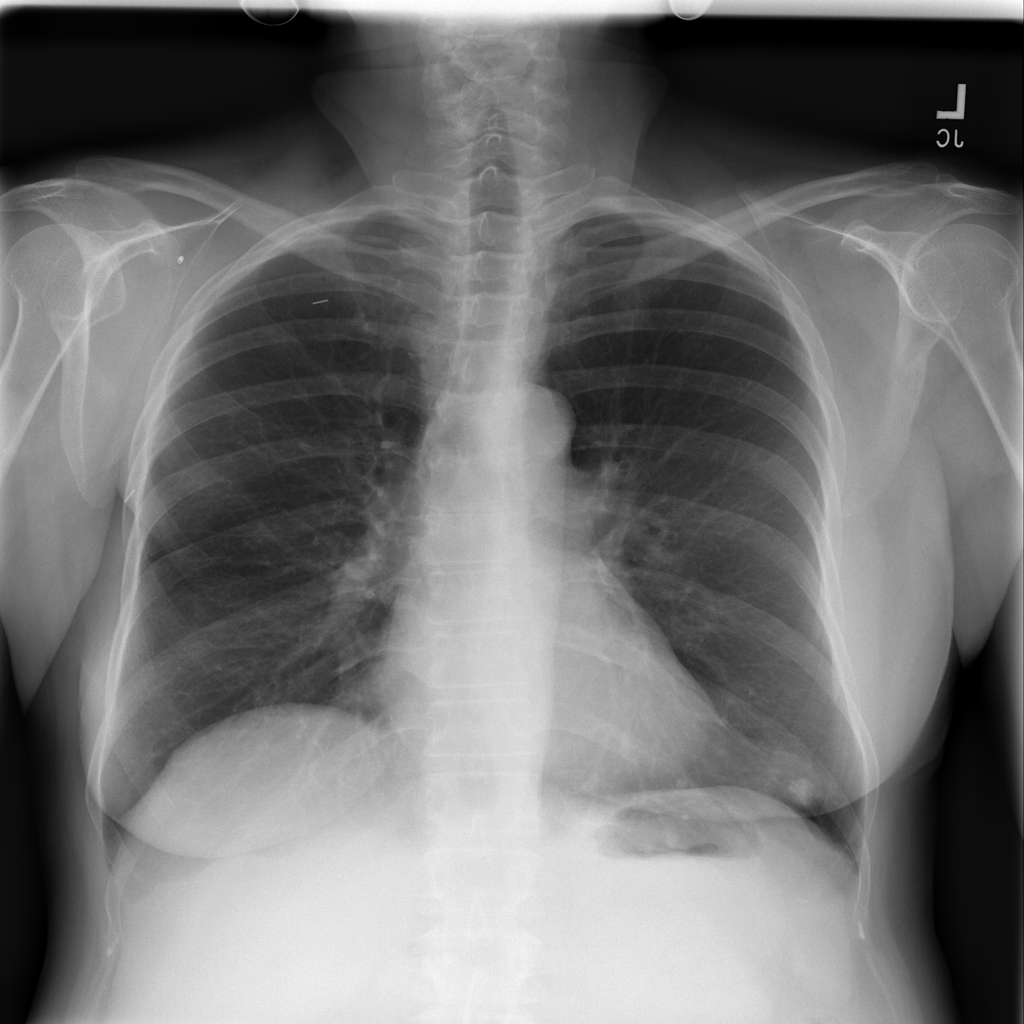

PAT-C4F1 · IMG-003Nodule

PAT-C4F1 · IMG-003

AP